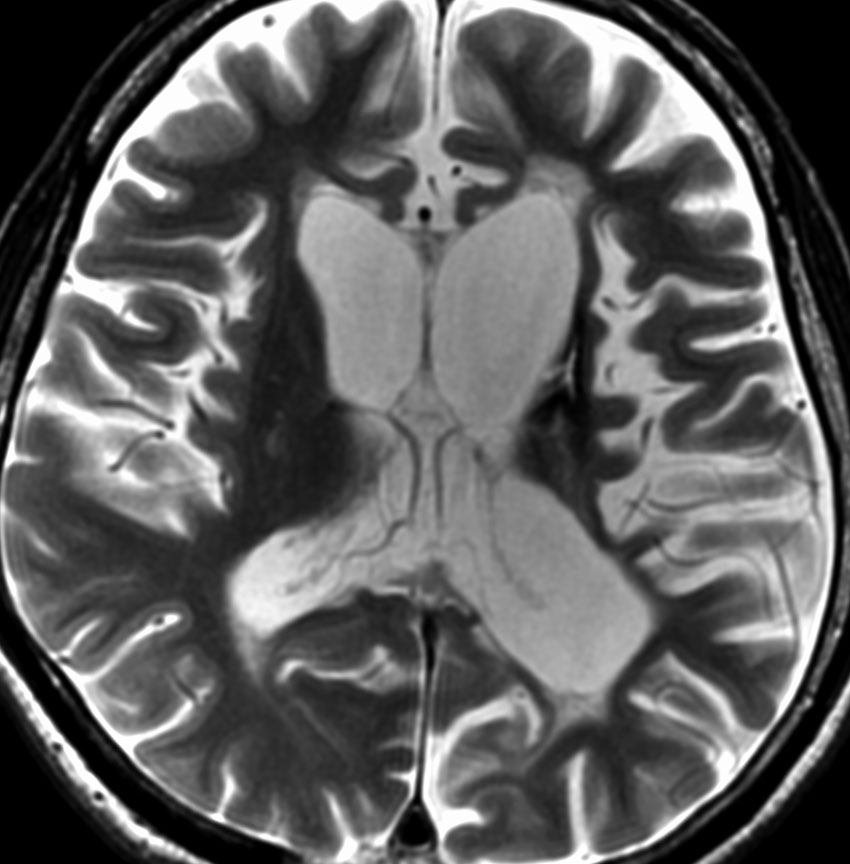

10代の男児で,非常にゆっくり1年くらいかけて左片麻痺が進行しました,痙性片麻痺です。落ち着きのない性格でもありました。血清HCG-beta 0.1で陽性でした。この病変は内包後脚の小さなものですから,定位生検術でさえもリスクが高いので行いません。出血のリスクというわけではなく,組織採取で内包高脚のcompactな白質を損傷して症状を悪くするからです。ご両親とよく話し合って病理診断なしで治療を開始します。ICE化学療法4コースと全脳照射25.2Gy/14fr で治療しました。ICE化学療法開始後からは片麻痺の悪化傾向が停止して,症状が改善傾向に向かいました。やがて,走れるようにもなりました。